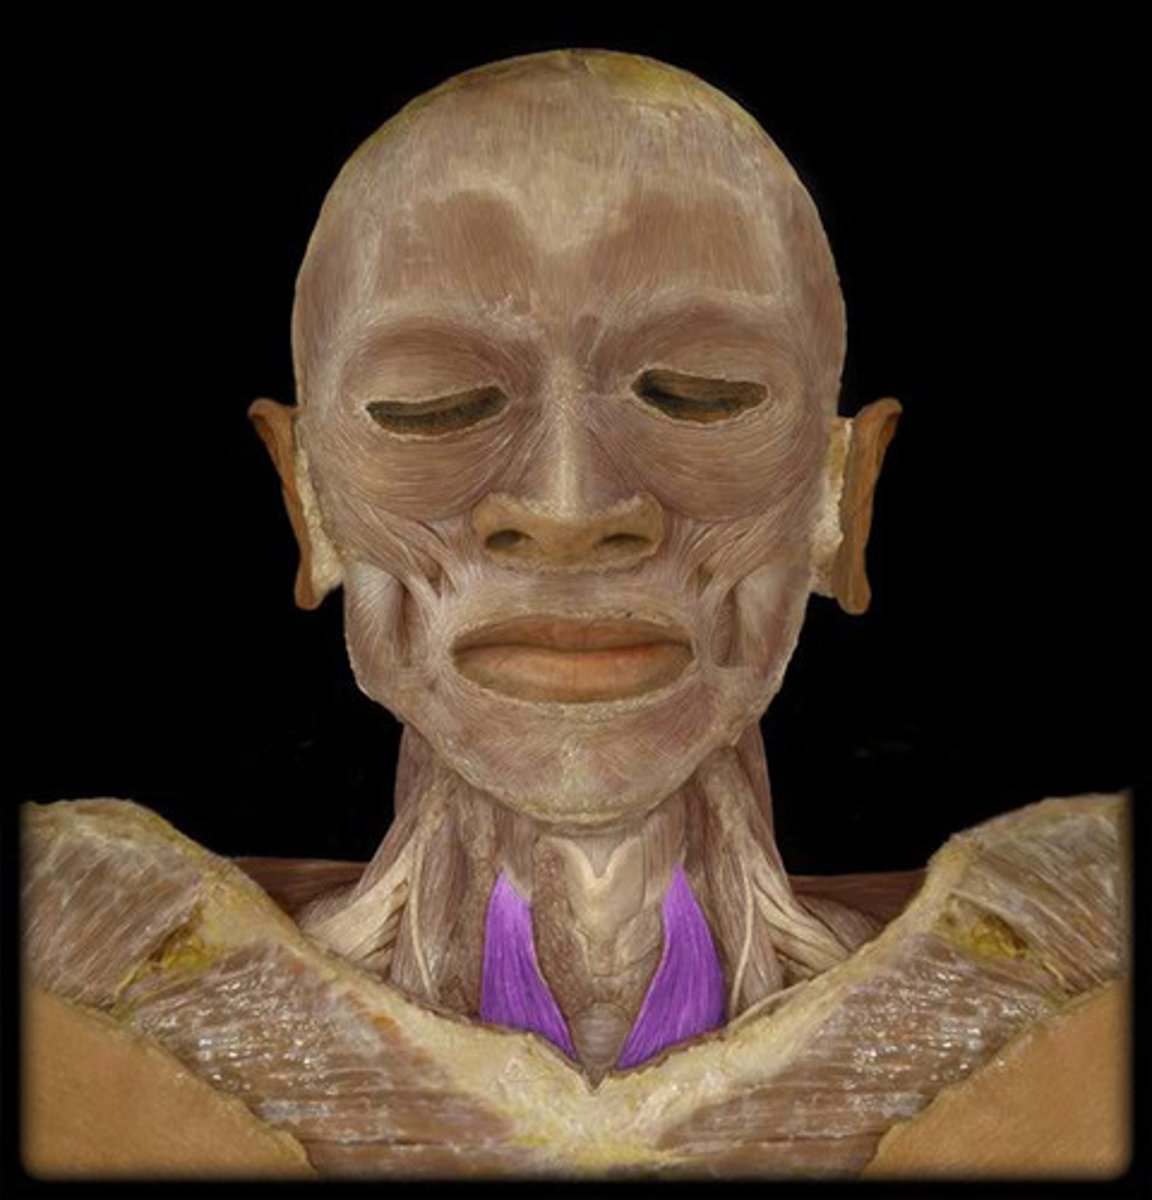

Sternocleidomastoid

Origin: Manubrium of sternum; medial 1/3 of clavicle

Insertion: Mastoid process of temporal bone

Action: head tilt, rotating head

Scalene

Origin: Transverse process of all cervical vertebrae

Insertion: Ribs 1-2

Action: helps breathe by elevating upper ribs, flexes head, rotates head side to side